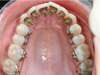

Après Orthodontie linguale Invisible Incognito, un fil est collé sur la face linguale des dents pour stabiliser le résultat.